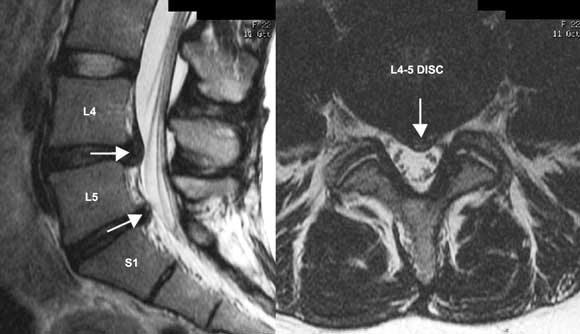

Case study 2 — back injury with neural symptoms

A 25-year-old woman with a 2-week history of gym-related back injury, some “soft” left leg neural symptoms (radicular pain and pins and needles) and signs (positive slump test and straight leg raise but intact reflexes, power and sensation). Clinical examination in this scenario can often confirm a diagnosis of likely lumbar disc prolapse.20 Differential diagnosis: Very likely to be a mild to moderate acute lumbar disc prolapse in this age group. Imaging options: X-ray is probably of minimal use and represents unnecessary radiation in a young woman. Surgery is probably not going to be indicated if neural signs are soft (ie, no reflex or sensory changes or wasting). An initial trial of a few weeks of conservative treatment based on the provisional clinical diagnosis alone (ie, without any immediate imaging) is reasonable if no complicating features are present.9 If this trial of treatment fails, or particularly if complicating features are present, imaging is indicated. Although a computed tomography (CT) scan (available on Medicare) would be sufficient to diagnose a disc protrusion, this carries an undesirable radiation risk in a young woman.21 Thus, despite its expense, an MRI scan (available on Medicare only with specialist referral) is the preferred imaging test (Figure). A positive result will confirm the cause and exact level of radicular irritation. This will assist management if conservative measures are not working and a second line of treatment is needed (eg, guided peri-neural cortisone injection). |